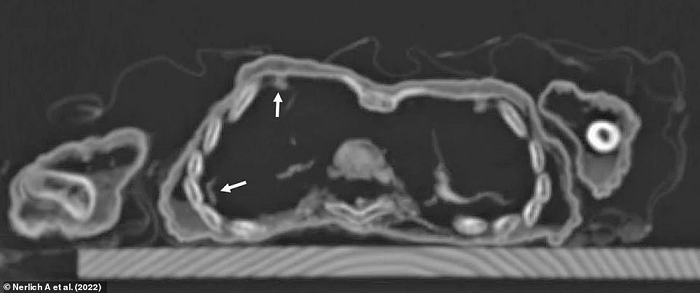

Tuy nhiên, kết quả chụp CT thể hiện xương sườn của cậu bị biến dạng, dấu hiệu của căn bệnh chuyển hóa xương (Metabolic Bone Disease - MBD) thường được thấy trong các trường hợp mắc bệnh còi xương nghiêm trọng. Hình ảnh chụp cắt lớp cũng cho thấy tình trạng đặc trưng của bệnh viêm phổi.